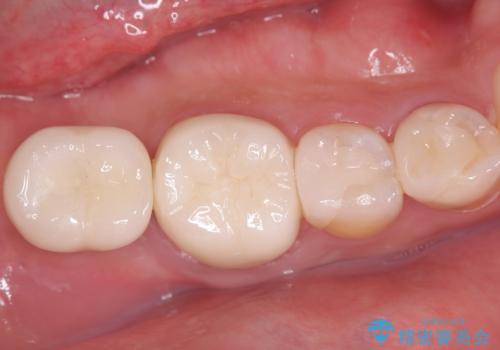

- 治療計画

- 患者様は、右側の奥歯でしっかり噛めないことを主訴に来院されました。診察の結果、右上6・右下6の根管治療が不十分で、感染のリスクがある状態と判断。これらの歯は再根管治療を行い、セラミッククラウンで補綴することにしました。また、右上7・右下7は欠損しており、噛み合わせを回復するためにインプラント治療を計画しました。

まず、右上6・右下6の根管治療を再度行い、根の状態をしっかり整えた上で、セラミッククラウンを装着しました。さらに、欠損していた右上7・右下7にはインプラントを埋入し、セラミッククラウンを装着。治療後は、「奥歯でしっかり噛めるようになり、不安なく食事ができるようになった」と患者様にも大変ご満足いただきました。